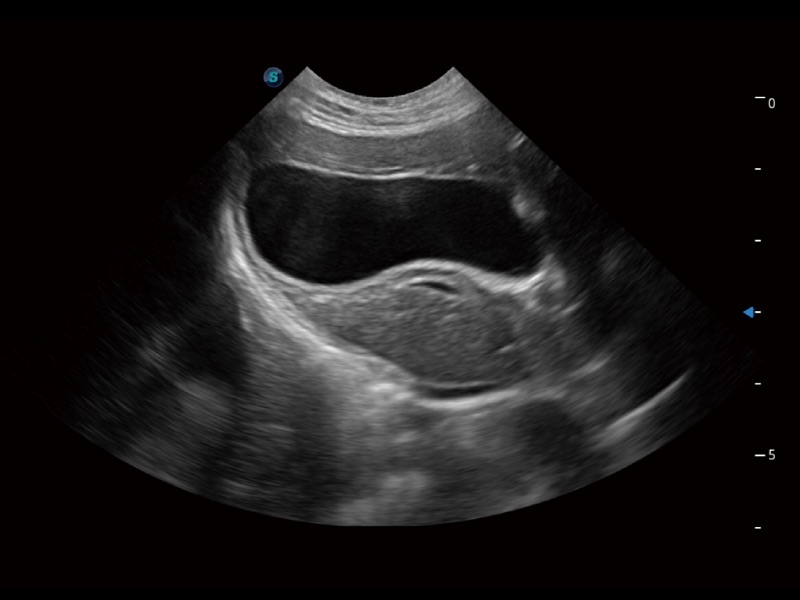

优异的基础图像

(猫)胆囊

(猫)肺动脉血流频谱